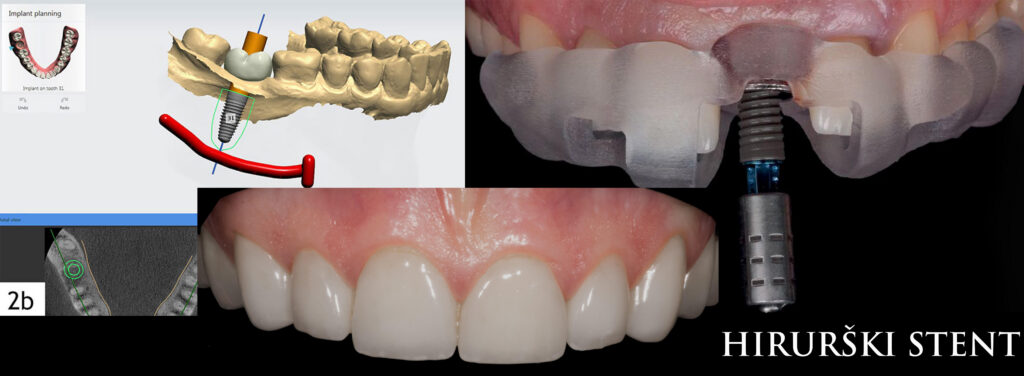

Denture also serve us for further producing of surgical guide.

And we use the surgical guide to accurately, digitally install your all on 4 dental implants in precisely planned positions.

Do not worry about the precision, at Queen clinic whole procedure is digitized and therefore very precise.

In order to manipulate with a gum as little as possible and cause almost no trauma during dental implants installation, we place implants with the help of digital technologies and a surgical stent.

The surgical stent allows us to precisely insert dental implants in a predetermined position. Thus, we get significant help and guidance during implantation and reduce the need to deatach the gums. The less manipulation with the gums, the easier and faster the patient`s recovery.